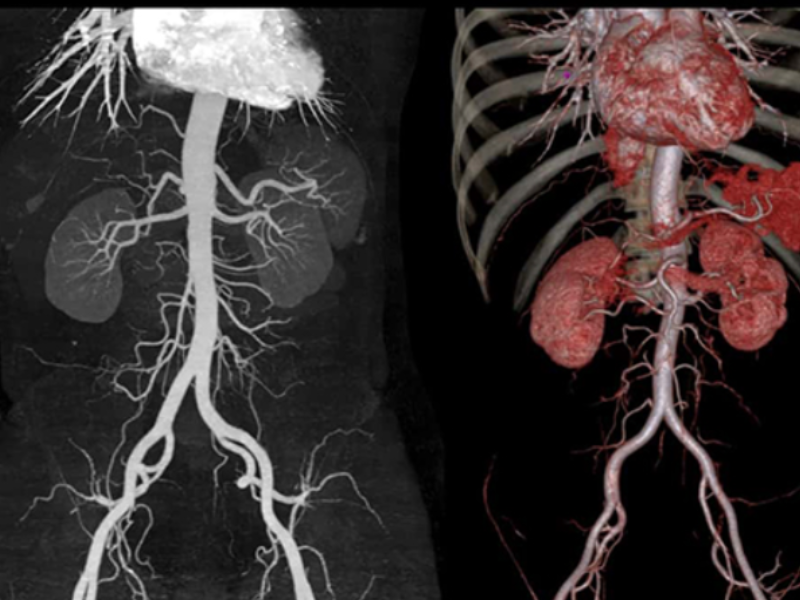

Fine Vascular Structure